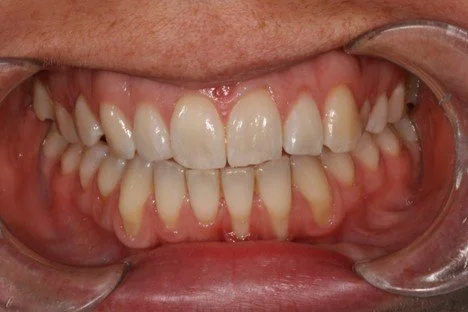

Periodontitis, also known as gum disease, is a common chronic condition that currently affects approximately nine million Australians. It derives from bacteria under the gum that causes inflammation, which leads to destruction of the periodontal ligament and bone holding the tooth.

Untreated periodontitis leads to destruction of the supporting bone around teeth and can eventually lead to the loss of a tooth or several teeth and is the leading cause of tooth loss in people of 40 years of age.

Gum recession occurs when the gum line pulls away from the teeth, exposing the roots and leading to sensitivity, a “long-tooth” appearance, and increased risk of decay. it can develop from factors such as periodontal disease, aggressive brushing, genetics, or teeth grinding.